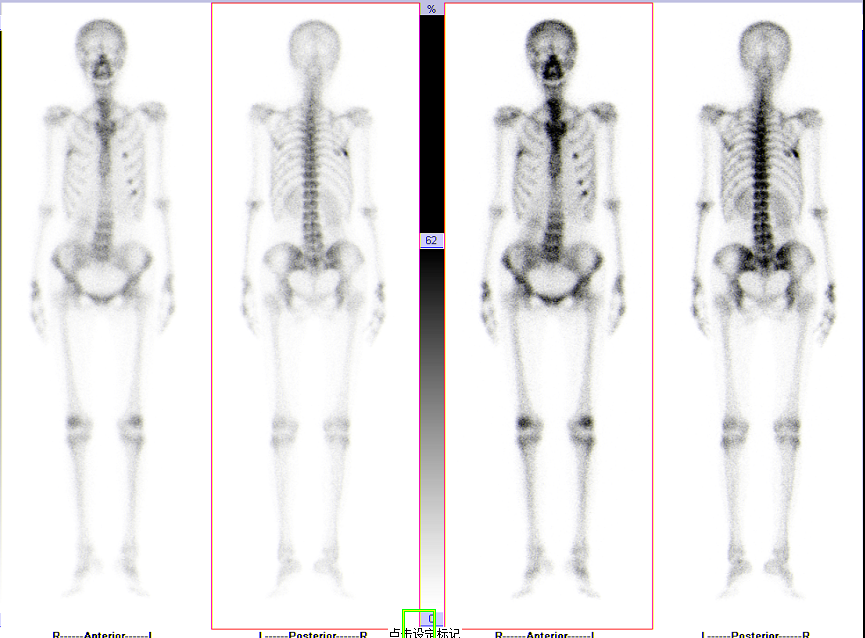

全身多发骨转移